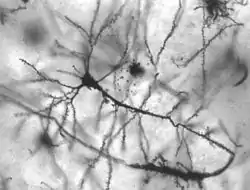

أمراض الجهاز العصبي تضر بعض الأمراض والإصابات بالجهاز العصبي.[3][4][5] ويصعب إصلاح محاوير الجهاز العصبي المركزي بعد تلفها الكبير. ولكن يمكن لبعض الأعصاب في الجهاز العصبي المحيطي استرداد وظيفتها إذا كان الضرر طفيفًا.

تتجمع معظم العَصبونات التي تؤدِّي وظيفة محددة في منطقة واحدة من الدماغ. وبسبب هذا الانتظام التجميعي الذي يسمى توضيع الوظيفة، فإن العطب أو الضرر الجزئي في الدماغ، لا يؤدي إلا لفقدان تلك الوظائف المسؤول عنها ذلك الجزء. ولكن قد يصدف أن تتولى بعض الأجزاء السليمة من الدماغ عمل تلك الأجزاء التالفة مؤدية إلى ما يُسمى باستعادة الوظيفة.